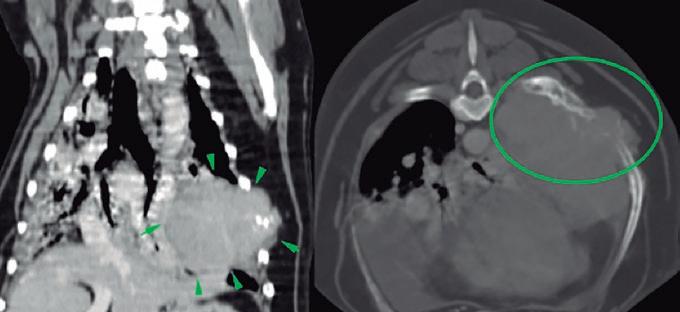

La responsabilidad de los artículos, reportajes, comunicados, etc. recae exclusivamente sobre sus autores. El editor sólo se responsabiliza de sus artículos o editoriales. La ciencia veterinaria está sometida a constantes cambios. Así pues es responsabilidad ineludible del veterinario clínico, basándose en su experiencia profesional, el correcto diagnóstico de los problemas y su tratamiento. Ni el editor, ni los autores asumen responsabilidad alguna por los daños y perjuicios, que pudieran generarse, cualquiera que sea su naturaleza, como consecuencia del uso de los datos e información contenidos en esta revista. De acuerdo con la normativa vigente en materia de protección de datos Grupo Asís Biomedia, SL., es responsable del tratamiento de sus datos personales con la finalidad de enviarle comunicaciones postales de nuestras revistas especializadas, así como otras comunicaciones comerciales o informativas relativas a nuestras actividades, publicaciones y servicios, o de terceros que puedan resultar de su interés en base a su consentimiento. Para ello, Grupo Asís podrá ceder sus datos a terceros proveedores de servicios de mensajería. Podrá revocar su consentimiento, así como ejercer sus derechos de acceso, rectificación, supresión, oposición, limitación y portabilidad enviando un correo electrónico a protecciondatos@grupoasis.com, o una comunicación escrita a Grupo Asís en Centro Empresarial El Trovador, planta 8, oficina I, Plaza Antonio Beltrán Martínez 1, 50002, Zaragoza (España), aportando fotocopia de su DNI o documento identificativo sustitutorio e identificándose como suscriptor de la revista. Asimismo, si considera que sus datos han sido tratados de forma inadecuada,